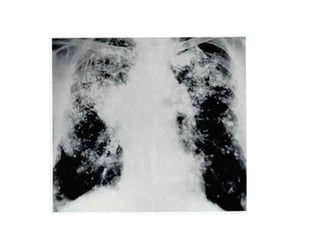

PNEUMOCONIOSE DIATOMITICA

+ DPOC

• BM, masculino, 56

anos,trabalha com terra

diatomática (20 anos);

doente há 5

anos, dispnéia, tosse

produtiva; fumante 20

cigarros/dia;

roncos, padrão obstrutivo

em grau moderado.